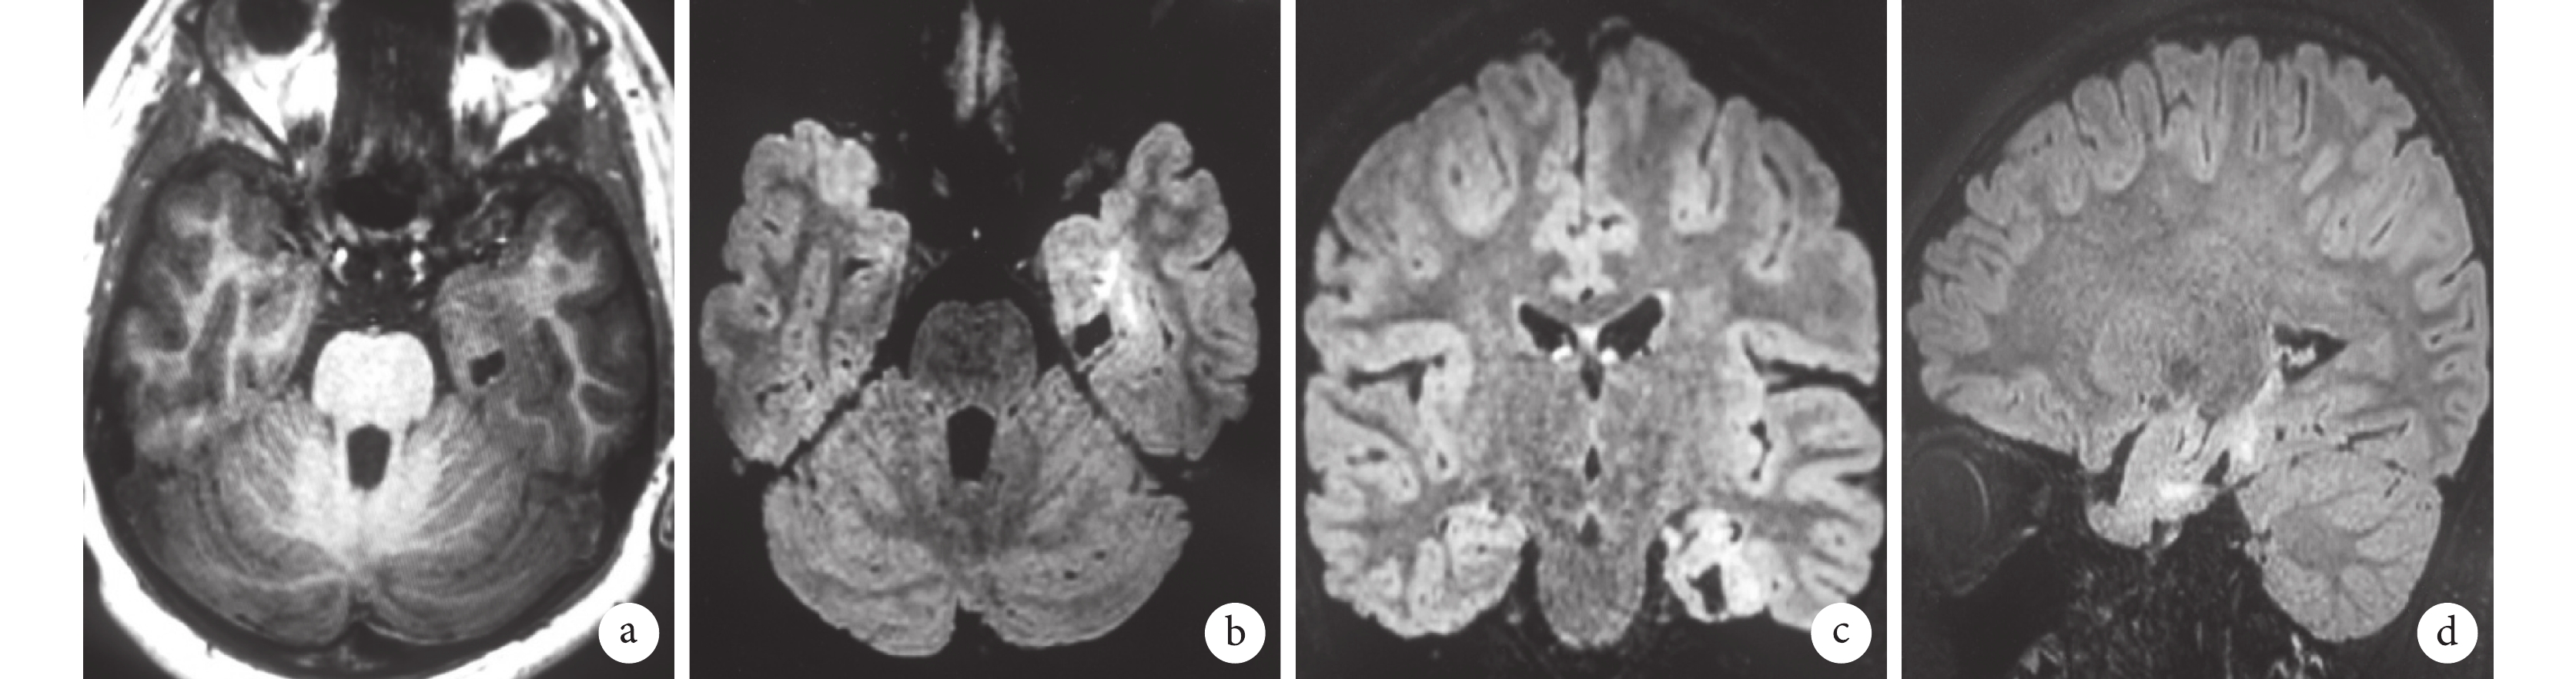

a,b. T1WI,左側枕葉局灶性灰白質分界模糊及相應皮層增厚;c,d. T2WI-FLAIR,病變部位 T2WI/FLAIR 灰、白質信號增高,并可見從皮質延伸到側腦室的帶狀高信號灶(transmantle sign)

Figure1. The patient one male,8 years-old. 3D high resolution MRI,frequent seizures,postoperative pathological diagnosis confirmed FCD Ⅱb typea,b. T1WI,focal gray-white matter boundary blur on left occipital lobe and corresponding cortical thickening; c,d. T2WI-FLAIR,increased signals with T2WI/FLAIR in gray and white matter at the lesion site,a band of high-signal foci extending from the cortex to the lateral ventricle were found(transmantle sign)

42 例經病理證實為 FCD 的患兒中,5 例 MRI 為陰性,均為Ⅰ型患兒。37 例(88.1%)呈陽性征象,見表 1。FCDⅠ型 13 例(35.1%),顳葉 6 例、額葉 4 例、頂葉 2 例,中央區 1 例,主要 MRI 特征:8 例表現為局灶性灰白質分界模糊及相應部位皮質結構異常(增厚或變薄);3 例除上述兩種征象外,還具有 T2WI/FLAIR 白質信號的增高;2 例為局限性腦體積縮小。FCDⅡ型 17 例(45.9%),額葉 9 例、頂葉 4 例、島葉 2 例,中央區 2 例,此型未發現顳葉發病,主要 MRI 征象較多且復雜:3 例表現為局灶性灰白質分界模糊及相應部位皮質結構異常(增厚或變薄);7 例除上述兩種征象外,還具有 T2WI/FLAIR 灰、白質信號增高;9 例發現局灶性異常信號從皮質延伸到側腦室:拖尾征(transmantle sign),且均為Ⅱb 型患兒,4 例為尖端指向腦室的錐形異常信號,3 例為寬窄不等帶狀異常信號,1 例為條狀異常信號灶,1 例為斷續顯示的異常信號;3 例僅表現為異常的腦溝及腦回形態(圖 1)。FCD Ⅲ型共 7 例(18.9%),為在Ⅰ型的基礎上伴發的其他病變,其中海馬萎縮 2 例、胚胎發育不良性神經上皮瘤(Dysembryoplastic Neuroepithelial tumor,DNET)2 例、節細胞瘤 1 例、2 例軟化灶并膠質增生(圖 2)。